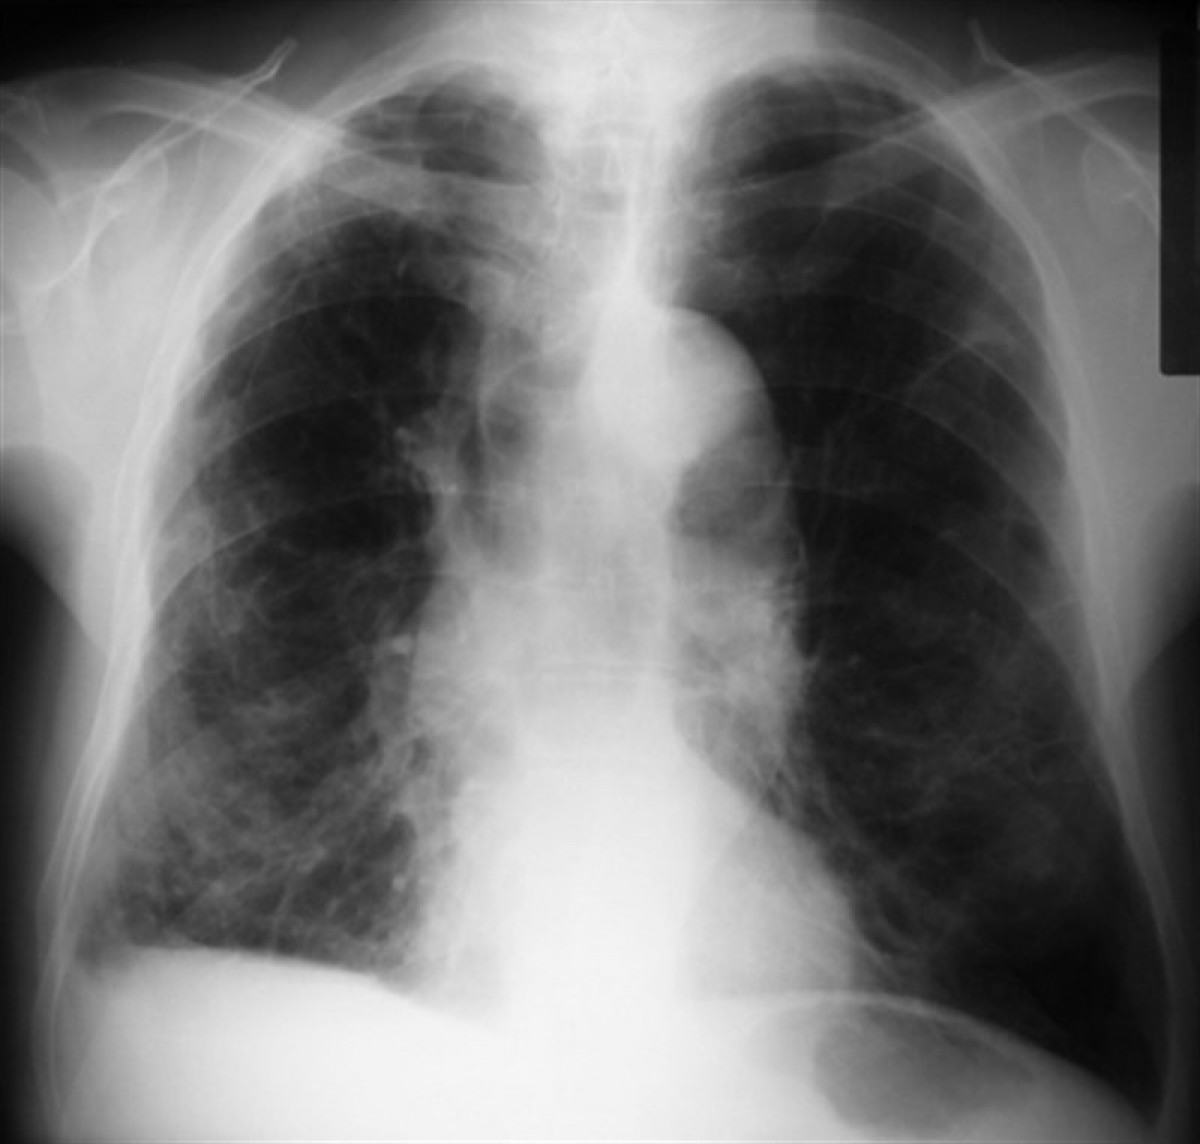

Pulmones

El estudio, dirigido por el neumólogo Bram van den Borst, incluyó a 124 pacientes que se habían recuperado de infecciones agudas por COVID-19. Visitaron la clínica de cuidados posteriores corona del centro médico de la universidad de Radboud, en Países Bajos. Los pacientes fueron examinados por tomografía computarizada y una prueba de función pulmonar, entre otros análisis.

Después de tres meses, los investigadores hicieron un balance, que reveló que el tejido pulmonar de los pacientes se estaba recuperando bien. El daño residual en el tejido pulmonar fue generalmente limitado y se observa con mayor frecuencia en pacientes que fueron tratados en la UCI.